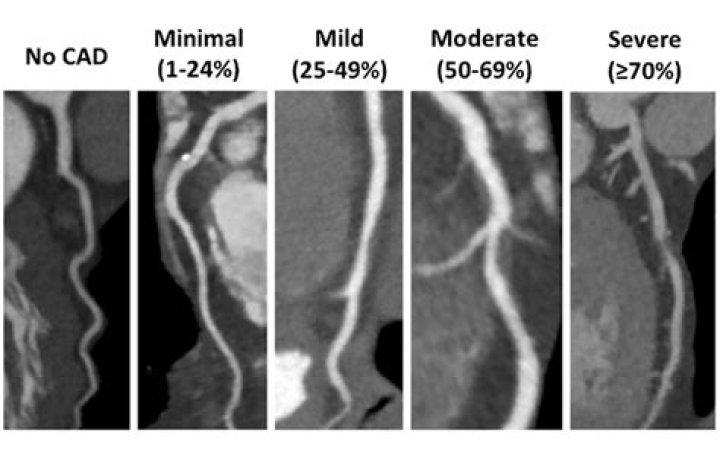

MRI is quite accurate in detecting blockages in the larger sections of the coronary arteries, but either misses or over diagnoses blockages in the smaller sections.

Visual cMRI assessment yielded sensitivity of 74.4% and specificity of 79.4% to predict > 50%DS, while SPECT showed sensitivity of 67.4% and specificity of 81.3%.